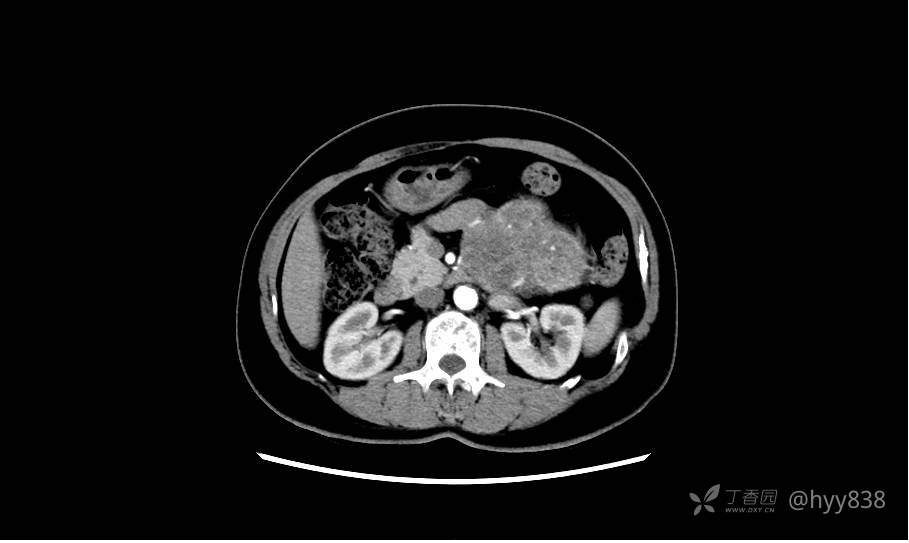

胰腺增强动脉期